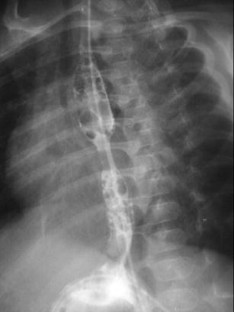

Anastomosis was achieved in all patients in an average of 4.8 days. One patient, with signs of early sepsis, was successfully treated with antibiotics. In four of the five patients, esophageal stenosis developed. At the time of this report, two patients were free of treatment and on an oral diet (after 26 months), two patients required periodic balloon dilatation, and one patient had recently undergone surgery due to recurrent esophageal stenosis not amenable to balloon dilatation.

Fig. 3